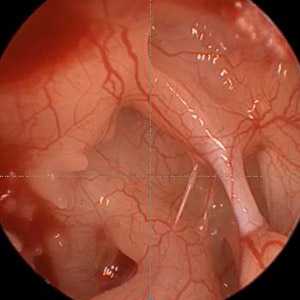

Endoskopischer Blick in Recessus fazialis und Sinus tympani